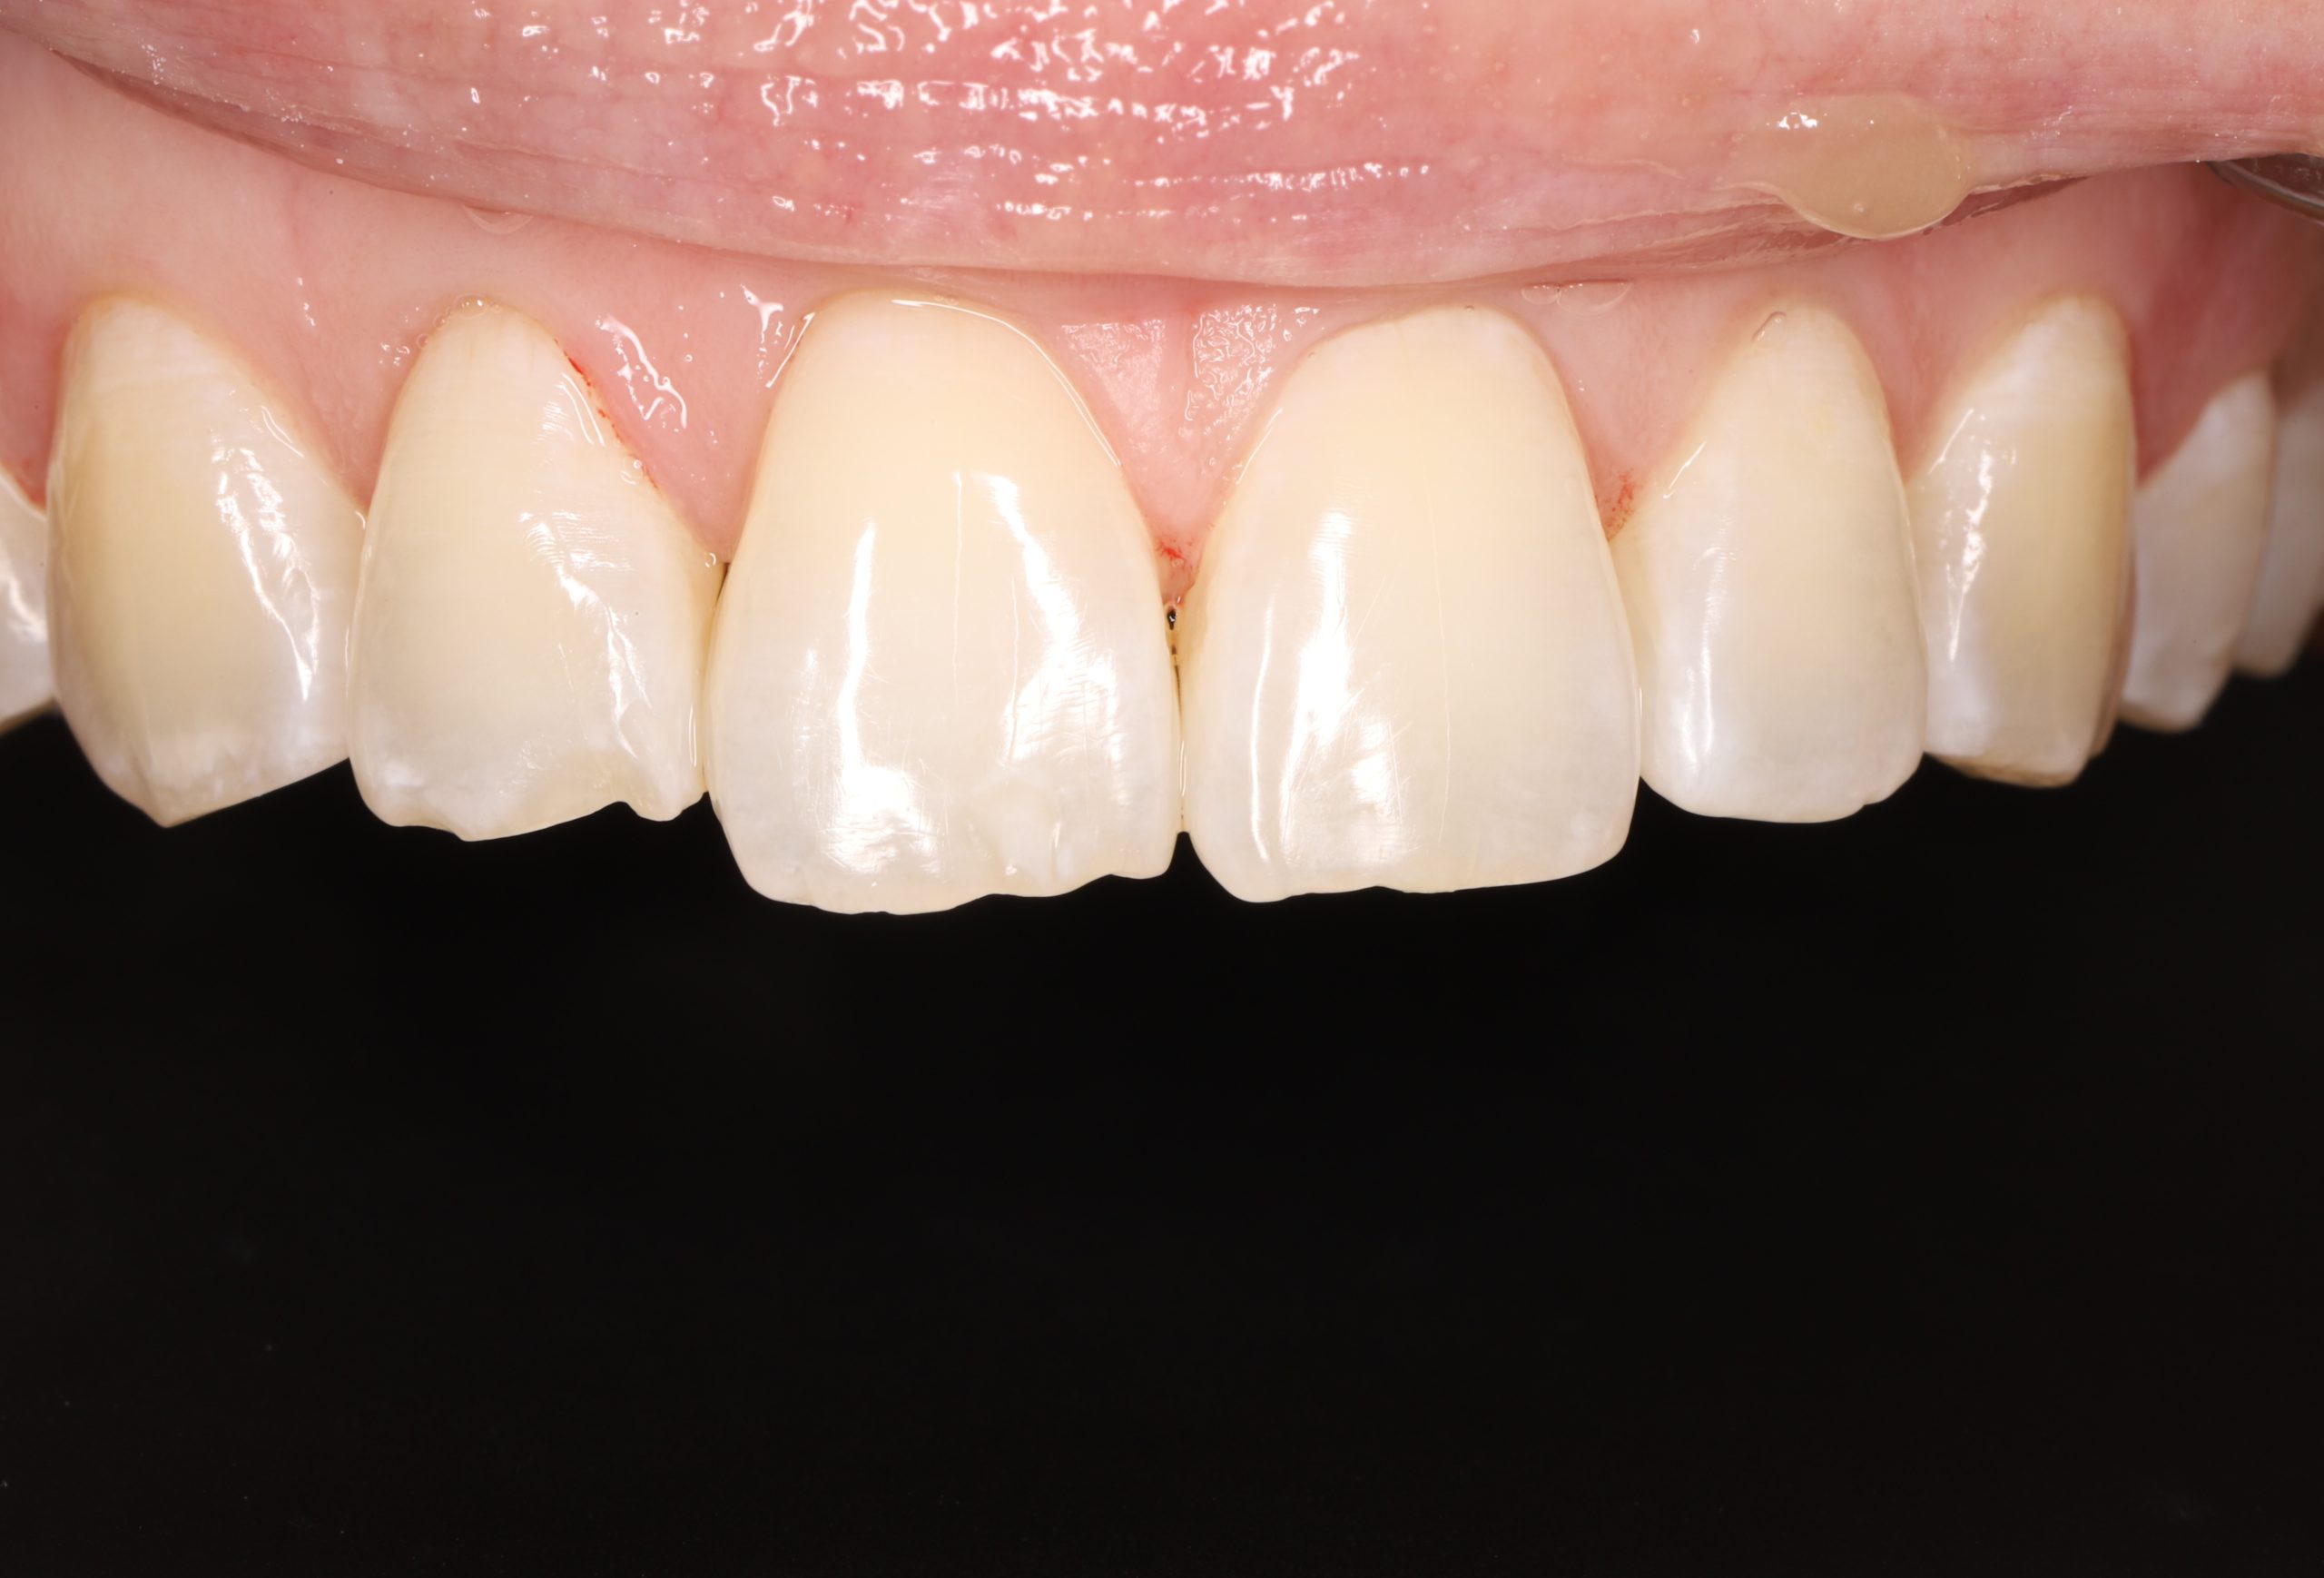

3. Layering the Composite Resin

The tooth-coloured resin is applied in thin layers and shaped carefully to match natural anatomy. For front-tooth work, we may combine several shades for a lifelike result.

5. Final Polishing and Bite Adjustment

We contour and polish the surface to a high gloss and ensure your bite feels natural in all positions.

Aesthetic and Natural-Looking

The material matches your enamel, blending into the smile with virtually invisible transitions.